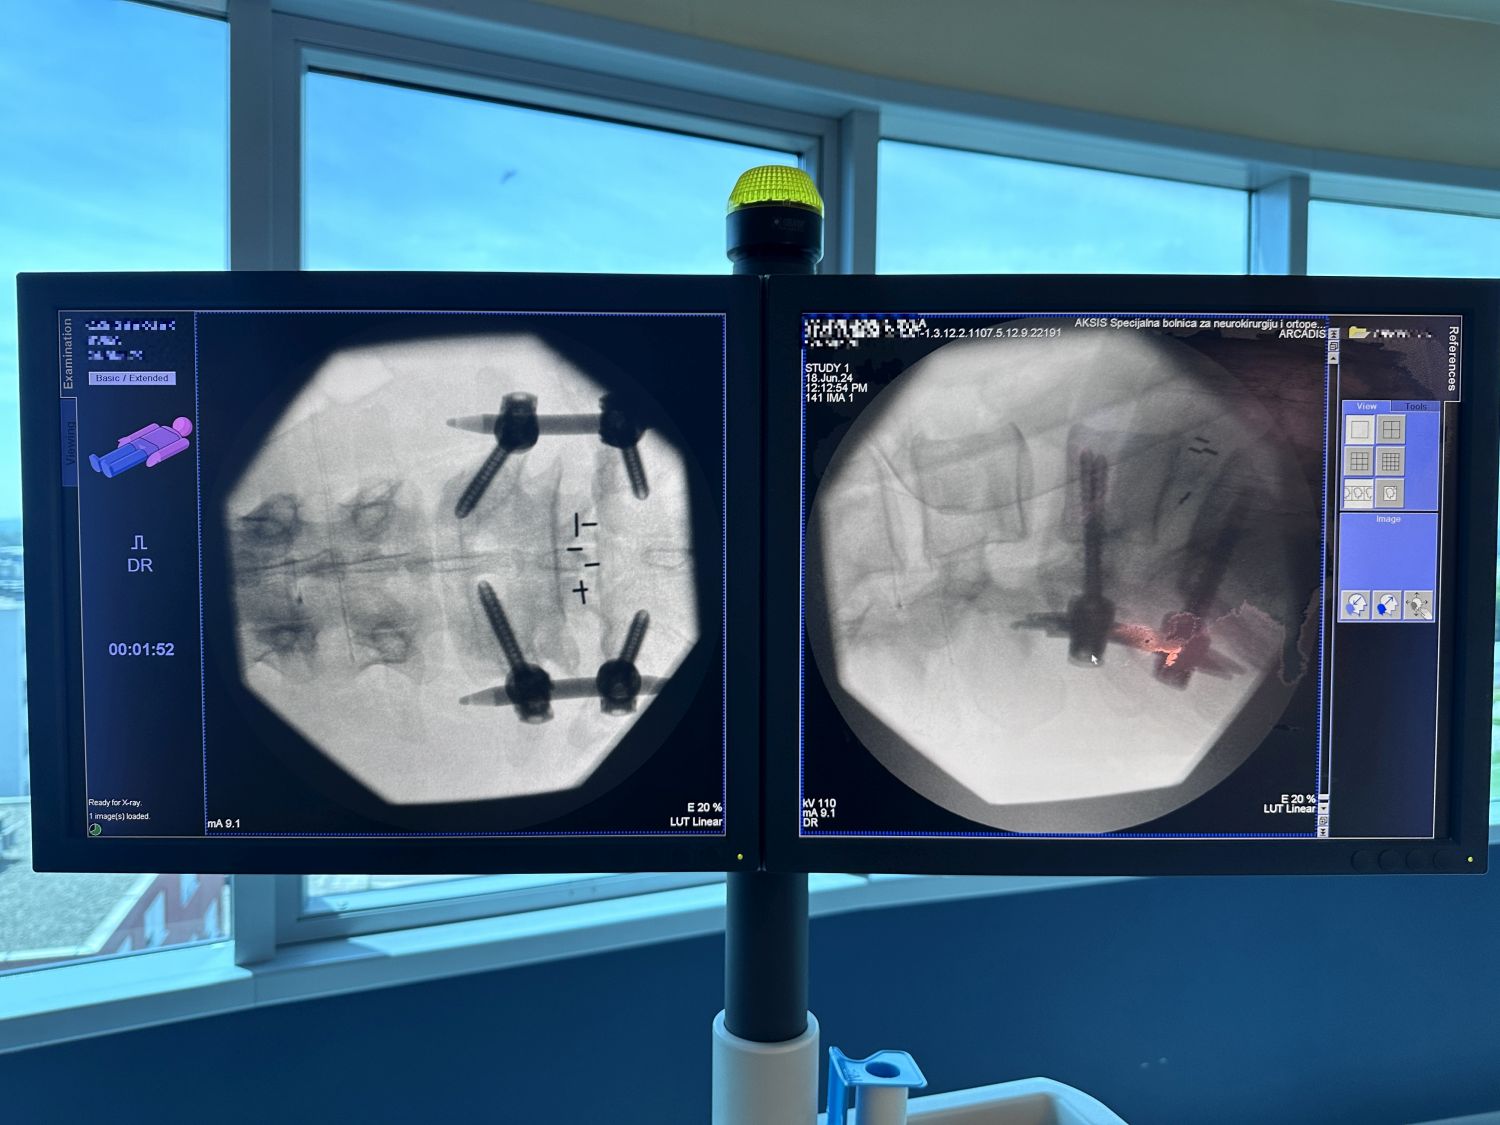

We are proud of our commitment and top results in spinal neurosurgery. In the last few days our extraordinary team performed two advanced and demanding spine surgeries that brought relief and improved quality of life to patients – METRx micro-endoscopic posterior decompression of the cervical spine, and miniOpen TLIF spinal fusion.

Our experience, knowledge and technical capabilities allow us to perform the most complex surgeries with a high success rate. Thanks to advanced technology and continuous education our neurosurgeons provide the best possible care. See the pictures below that show the precision and innovation of our procedures.